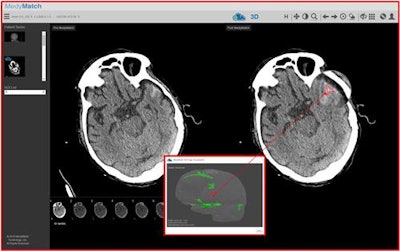

How will MedyMatch work with IBM Watson? The algorithm will be incorporated into the Watson environment at IBM installations, using a workflow designed to require minimal intervention by physicians. DICOM images from all noncontrast head CT exams will be automatically routed to MedyMatch, which will analyze the data and return to users an annotated image series highlighting suspicious areas that can be viewed alongside the original scans, using whatever PACS or viewer the physician is reading from.